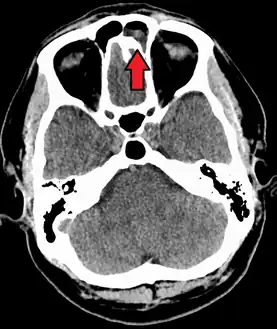

Maxillary sinusitis caused by a dental infection associated with periorbital cellulitis